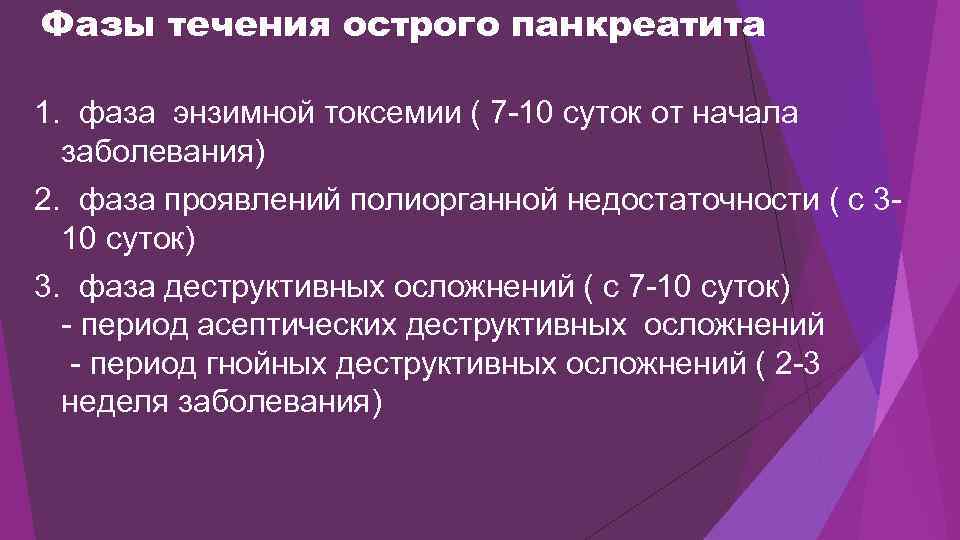

Фазы течения острого панкреатита 1. фаза энзимной токсемии ( 7 -10 суток от начала заболевания) 2. фаза проявлений полиорганной недостаточности ( с 310 суток) 3. фаза деструктивных осложнений ( с 7 -10 суток) - период асептических деструктивных осложнений - период гнойных деструктивных осложнений ( 2 -3 неделя заболевания)

Фазы течения острого панкреатита 1. фаза энзимной токсемии ( 7 -10 суток от начала заболевания) 2. фаза проявлений полиорганной недостаточности ( с 310 суток) 3. фаза деструктивных осложнений ( с 7 -10 суток) - период асептических деструктивных осложнений - период гнойных деструктивных осложнений ( 2 -3 неделя заболевания)